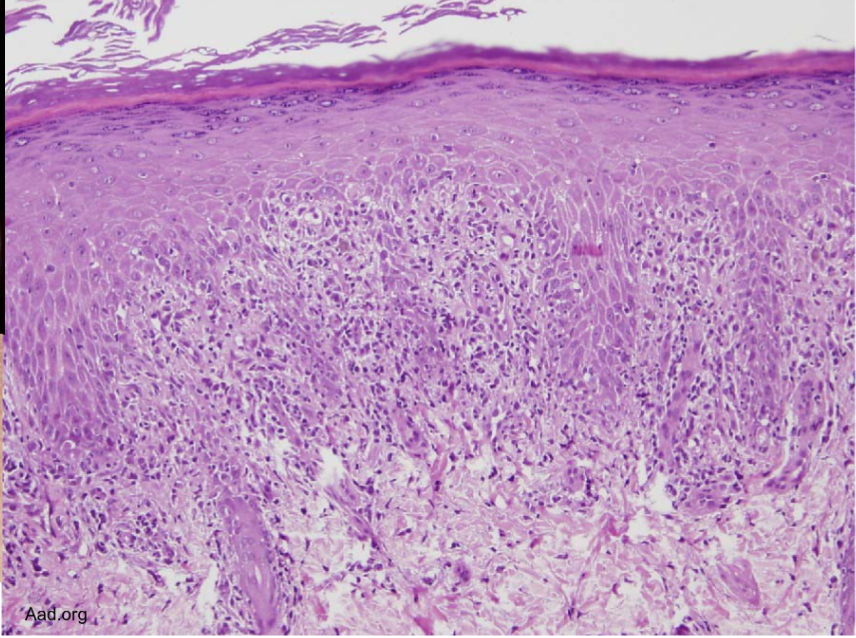

Bandlike infiltrate of lymphocytes @ dermoepidermal junction

Hyperkeratosis, hypergranulosis, sawtoothing (result of chronic basal cell layer injury)

lichen planus